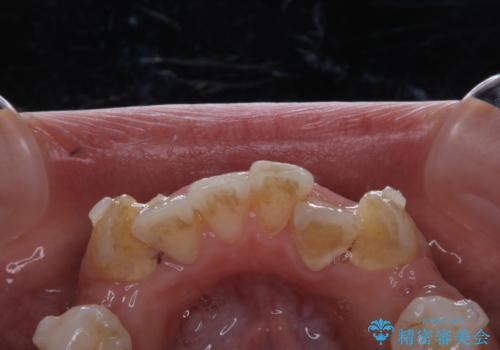

インビザラインで矯正中のコーヒーによる着色をきれいに除去

- インビザライン中に、コーヒーによる着色が気になるとのことでした。PMTC60分コースを行いました。

PMTC(保険外治療)は、毎日の歯磨きで落としきれない汚れや、コーヒ、紅茶・タバコのヤニなどの着色も除去します。目には見えない歯と歯の間・歯肉の境目・インビザライン中はアタッチメント周囲などに残っているプラーク(歯垢)もしっかり取り除きます。PMTCでは専門的な機械や材料を使用して、徹底的に汚れを除去するため、虫歯・歯周病・口臭予防などにつながります。